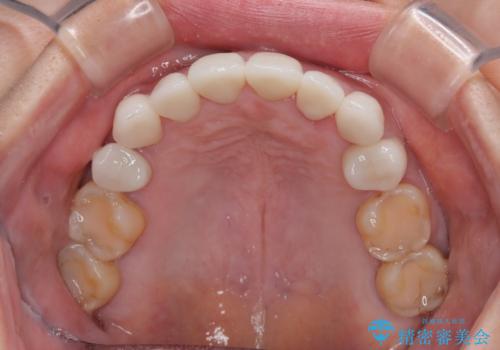

前歯のデコボコおよび奥歯の咬み合わせを改善するために、上顎左右の小臼歯を欠損スペースを利用して歯列を整え、矯正治療後に気になる上下前歯などをオールセラミッククラウンで美しく仕上げていくこととしました。

色や歯列が整ったことはもちろん満足いただけましたが、上顎の舌側転位していた前歯が綺麗に整ったことで違和感が減ったことを非常に喜んでいらっしゃいました。